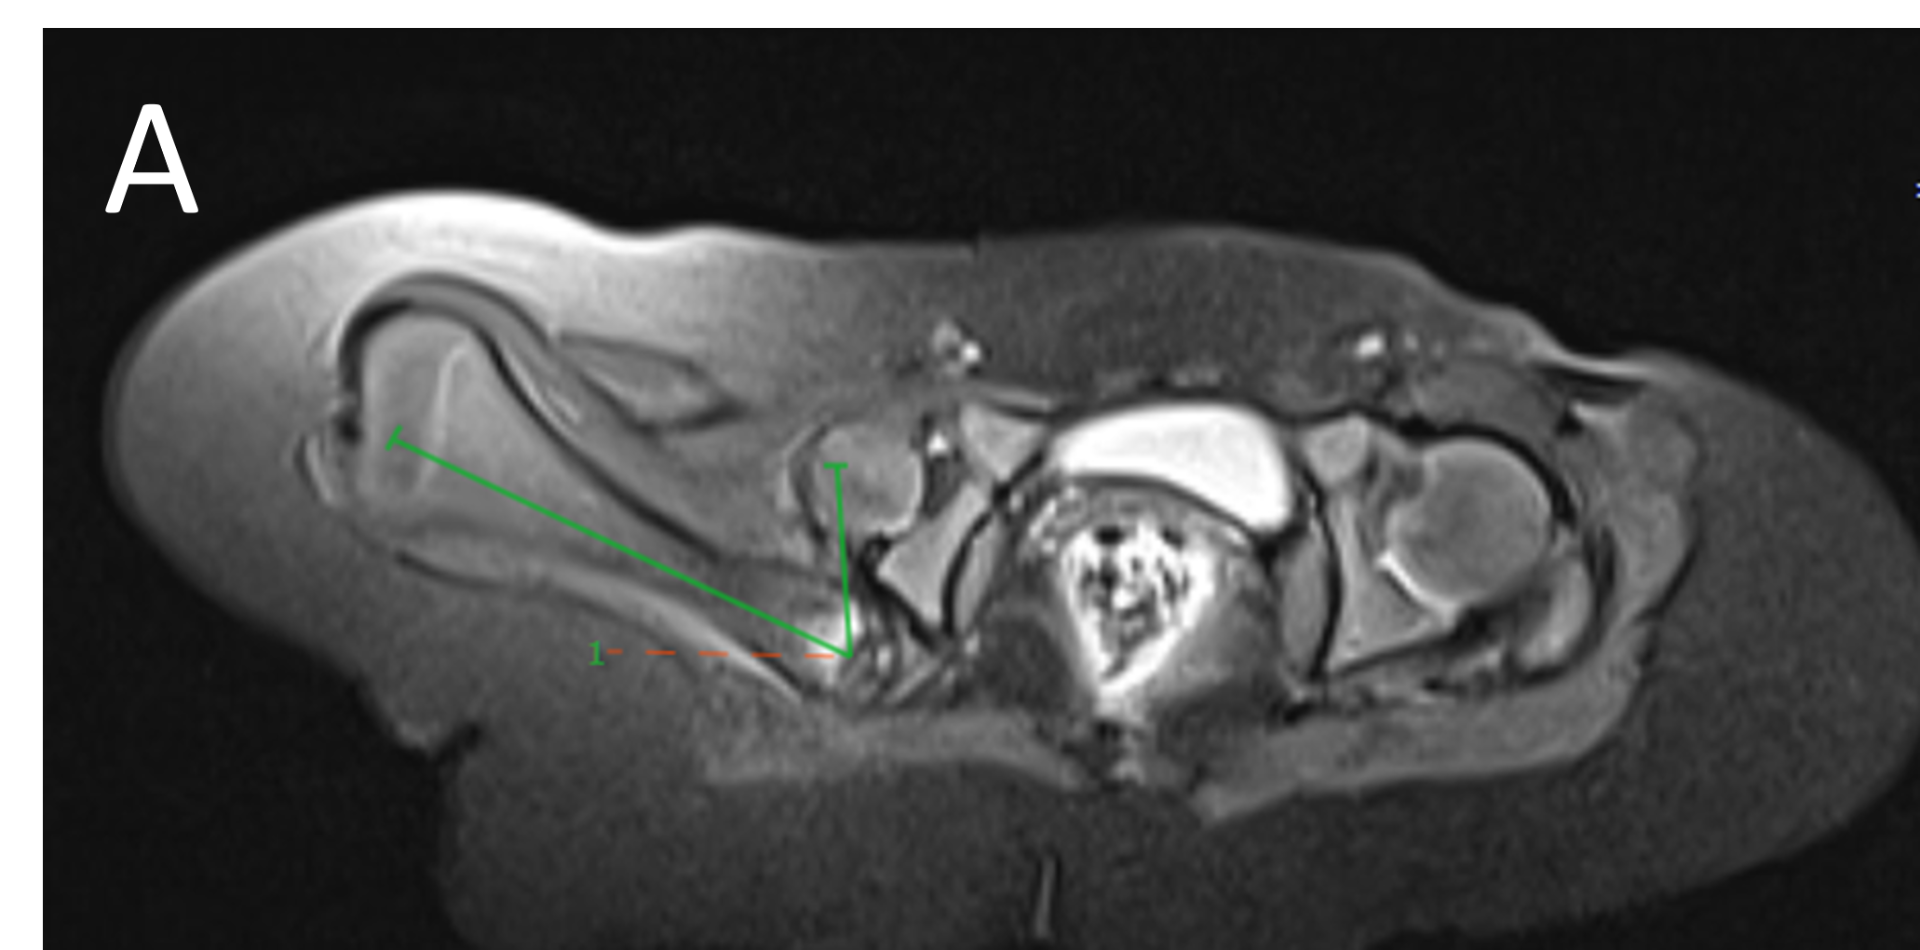

- A.LEGENDS – MR BILATERAL HIPS :Right femur is shortened, with a coxa vara deformity. Femoral shaft measures 7.2 cm in length. The acetabulum is moderately dysplastic and anteriorly rotated, But contains the femoral head. The femoral head and neck appear hypoplastic and posteriorly and externally rotated.